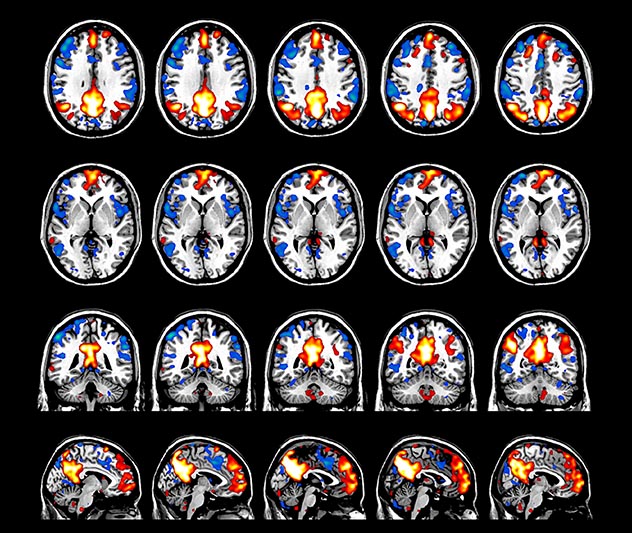

Imaging was performed using Ingenia 3T CX with a 32ch dS Head coil, TR 1.6 sec, TE 35 ms, voxel size 3.1 x 3.1 x 3.1 mm, 46 slices and Multiband SENSE factor 2. Image provided by Dr. Gispert

Default mode network as discovered by resting state fMRI in one participant of the ALFA cohort [7]. rs-fMRI allows us to find networks of brain regions with highly correlated activity and sustaining distinct brain functions. The default mode network (in warm color scale) is active when the brain is focused on introspective thinking and has been shown to be altered in Alzheimer’s. Interestingly, brain areas of this network are known to show abnormal levels of one of the pathological hallmarks of Alzheimer’s (b-amyloid deposition) in preclinical stages. We want to better understand the alterations of these brain networks in preclinical stages of Alzheimer's and explore their potential use as biomarkers.